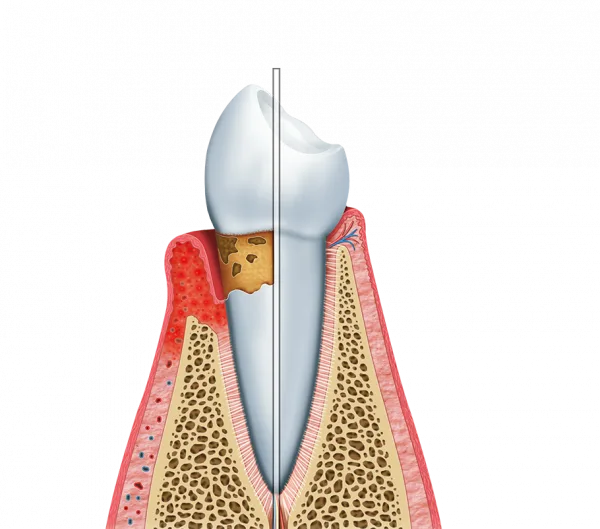

A cirurgia estética periodontal pode corrigir questões como gengivas excessivamente altas ou baixas, restabelecendo o equilíbrio visual necessário para uma face atraente.

A cirurgia estética periodontal possui a capacidade de redefinir o contorno dos tecidos moles de forma precisa. Isso resulta em um sorriso mais harmonioso e equilibrado com os lábios:

Eliminação de assimetrias visíveis;

Correção do “sorriso gengival” (exposição excessiva);

Recobrimento de raízes expostas para um visual uniforme.

O procedimento ajuda a remover imperfeições que podem desviar a atenção da beleza natural dos dentes. Com as gengivas alinhadas, o visual torna-se mais agradável e as proporções faciais são respeitadas.